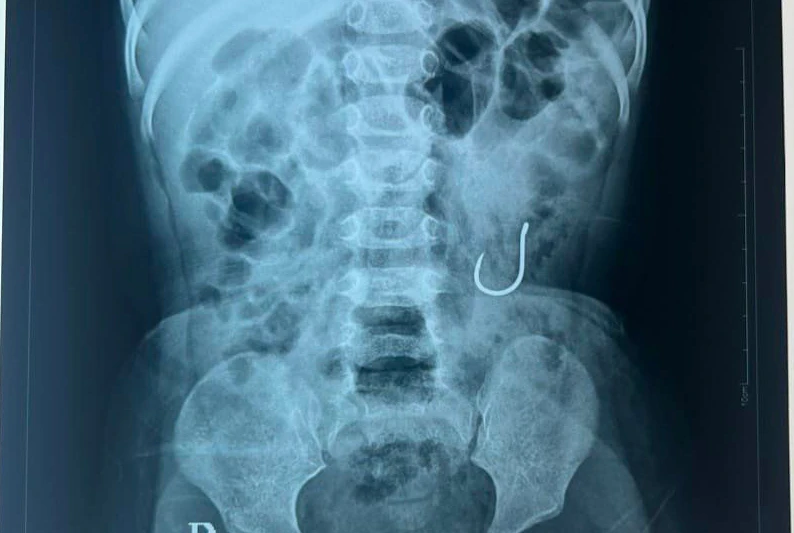

Qua thăm khám, các bác sĩ đưa ra chẩn đoán, bệnh nhi có dị vật tại đường tiêu hoá (lưỡi câu). Các bác sĩ đã hội chẩn và đưa ra hướng điều trị là cho bệnh nhi nhịn ăn, uống, nuôi dưỡng tĩnh mạch và để lưỡi câu tự ra ngoài qua đại tiện (bệnh nhi còn quá nhỏ, nếu phẫu thuật có khả năng ảnh hưởng biến chứng sau này).

Đến tối 27/6, dị vật lưỡi câu đã được đẩy ra khỏi cơ thể bệnh nhi T.A.T. an toàn qua đường đại tiện. Hiện tình trạng bệnh nhi ổn định và tiếp tục được theo dõi Bệnh viện Sản Nhi tỉnh.